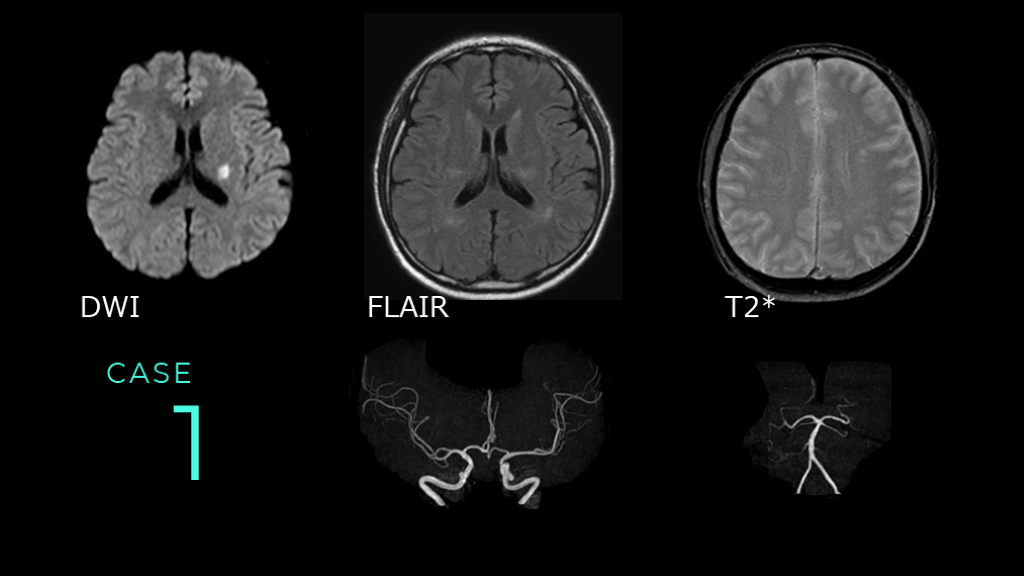

1 CASE DWI FLAIR T2*

1 CASE DWIでは基底核レベルのスライスで左側に高信号病変を認める。FLAIRでは同病変は等信号である。 T2*ではmicrobleedsは認めない。 DWI      FLAIR

1 CASE MRAでは、前方循環系・後方循環系ともに目立った血管狭窄病変は認められない。

1 CASE コメント: DWI HIGH、FLAIR ISOの信号変化であり、超急性期の脳梗塞病変です。左の中大脳動脈(MCA)の穿通枝領域梗塞。 脳梗塞疑いの場合には、血管支配に一致した病変であるかどうかを検討しています。 これは典型的なラクナ梗塞画像。